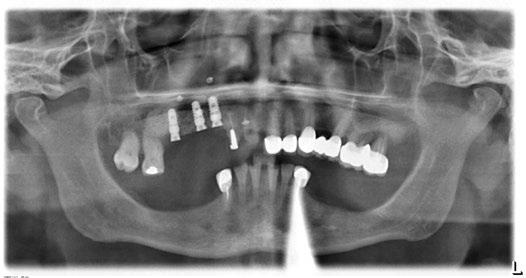

Figura 16. Ortopantomografía postoperatoria.

Figura 17. Resultado final.

directamente a cabeza de implante para realizar una prótesis dentoalveolar de cerámica de 3 piezas, que equilibraran la oclusión y dieran soporte al labio y la mejilla (Figuras 14-17)

Durante el primer mes tras la intervención la paciente presentó epífora del ojo izquierdo que se resolvió de forma espontánea. Al año acude a consulta refiriendo dolor localizado y celulitis subcutánea originada por tejido de granulación en el brazo de la conexión más anterior.

Tras realizar curetaje quirúrgico periimplantario y tras una semana

de tratamiento antibiótico con amoxicilina y ácido clavulánico, cede la infección. Al segundo año de seguimiento, el tratamiento permanece estable y no ha presentado más complicaciones biológicas, estructurales o protésicas.